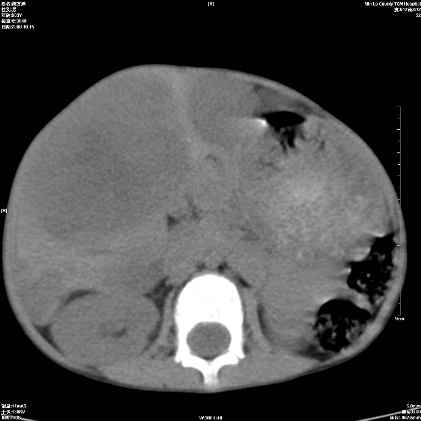

标题: PED1609:男性,3岁。彩超示肝Ca. [打印本页]

标题: PED1609:男性,3岁。彩超示肝Ca.

3岁;肝低密度灶;有钙化;有转移灶;考虑肝母细胞瘤;查afp

考虑神经母细胞瘤并肝转移